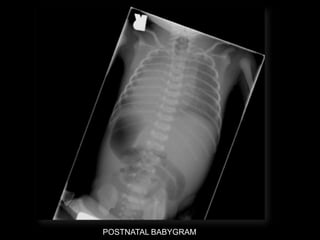

POSTNATAL BABYGRAM

-Cephalic

-Heart - right side

-Stomach โ€“ right side

-Liver โ€“ left side

-Des colon โ€“ right side

Situs Inversus Totalis

-Cephalic -Heart - rightside -Stomach โ€“ right side -Liver โ€“ left side -Des colon โ€“ right side